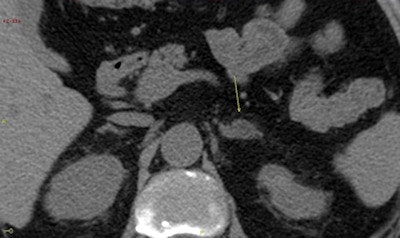

The new study is a breakthrough for determining how patients with silent adrenal tumors should be managed and which patients will benefit from a surgical approach, according to Dr. Guido Di Dalmazi.

"The most important aspect of this study is now we know more about the natural history of this disease and how we should treat patients," said Dr. Guido Di Dalmazi, a researcher and endocrinologist at the S. Orsola-Malpighi Hospital. "Due to the increased incidence of CV event and mortality associated with elevated cortisol levels, we can speculate that a surgical rather than nonsurgical approach will be beneficial in patients with a secreting tumor."

The next step is to study which specific patients will benefit from surgery and which from drug therapy, according to Di Dalmazi, who pointed to patients with bilateral disease as potential candidates for a medical rather than surgical approach.